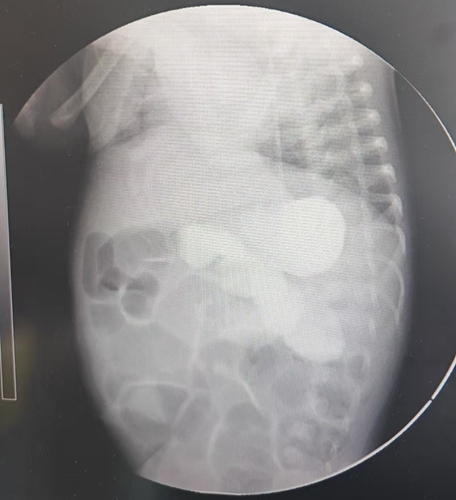

顏顏的人生從一開始就布滿荊棘。出生后,她因無法排出胎便,伴隨腹脹、嘔吐等癥狀,在當(dāng)?shù)蒯t(yī)院被確診為先天性巨結(jié)腸 —— 且是該病癥中最罕見也最嚴(yán)重的類型:全腸型先天性巨結(jié)腸,其發(fā)病率僅占所有先天性巨結(jié)腸病例的 1%-2%。

檢查結(jié)果不盡人意 —— 近3米長的腸道中,健康部分僅有15 公分!這意味著顏顏成了“短腸寶寶”,且病情尤其復(fù)雜嚴(yán)重,治療起來極為棘手。

針對(duì)顏顏的病情,新生兒外科宋華主任團(tuán)隊(duì)迅速制定了分階段治療方案。在保守治療滿一個(gè)月后,團(tuán)隊(duì)為她實(shí)施了第一次手術(shù)。術(shù)中不僅完成了回腸雙腔造瘺,還進(jìn)行了腸切除與腸吻合操作;術(shù)后腸活檢結(jié)果顯示,顏顏全腸神經(jīng)節(jié)細(xì)胞稀少 —— 這正是導(dǎo)致她腸道無法正常蠕動(dòng)的核心原因。